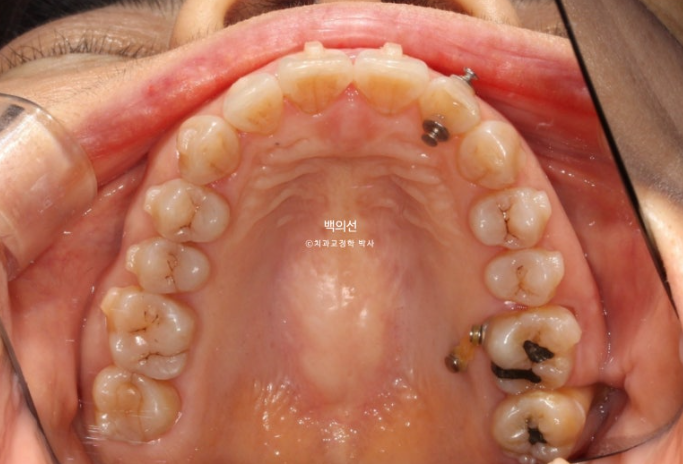

앞니 두 개가 튀어나와 돌출이며

아래 앞니는 치아가 많이 겹쳐져 있습니다.

특히 가운데 앞니와 옆 앞니는 50% 정도가 겹쳐진 상태

다른 문제가 하나 더 있습니다. 파란 화살표 치아는 신경치료 된 치아인데 뿌리끝에 염증이 있습니다.

인비절라인이 이와같이 치근단 염증이 있거나 잇몸이 약해 교정력이 가해지지 않아야할 치아들이 있는 경우 큰 장점이 있습니다.

치료의 처음부터 끝까지 치아이동이 없게끔 치료계획을 세우면, 약간 치아에 무리가 가지 않게 나머지 타겟치아들만 움직이면서 교정이 가능합니다.

입천장에 교정용 나사인 미니스크류를 1개 심고 정출된 제1구치 함입을 도모합니다.